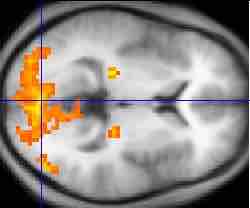

An fMRI of the brain

An fMRI scan showing regions of activation (in orange) including the primary visual cortex.

The fMRI is a series of MRIs that measures both the structure and the functional activity of the brain through computer adaptation of multiple images. Specifically, the fMRI measures signal changes in the brain that are due to changing neural activity. In an fMRI, a patient can perform mental tasks and the area of action can be detected through blood flow from one part of the brain to another by taking pictures less than a second apart and showing where the brain "lights up." For example, when a person processes visual information, blood rushes to the back of the brain, which is where the occipital lobe is located. FMRIs make it possible to show when things happen, how brain areas change with experience, and which brain areas work together. They have been used to study a wide range of psychological phenomena, including (but by no means limited t0) the neural activity of telling a lie, the differences between novices and experts when playing a musical instrument, and what happens inside our heads when we dream.